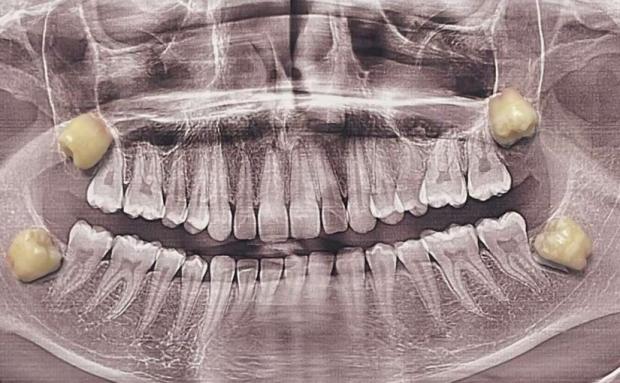

Навіть якщо зачатки зубів мудрості сформувалися, це не гарантує, що вони проріжуться. Приблизно у 80% молодих дорослих хоча б один зуб мудрості залишається ретинованим, тобто прихованим у щелепі.

Такі зуби можуть рости під кутом, упиратися у сусідні зуби чи взагалі не мати можливості вийти назовні. Саме ретиновані зуби найчастіше стають джерелом проблем — болю, запалення, інфекцій чи зміщення зубного ряду.

Рішення про видалення завжди ухвалюється індивідуально, на основі огляду та рентгенівських знімків.